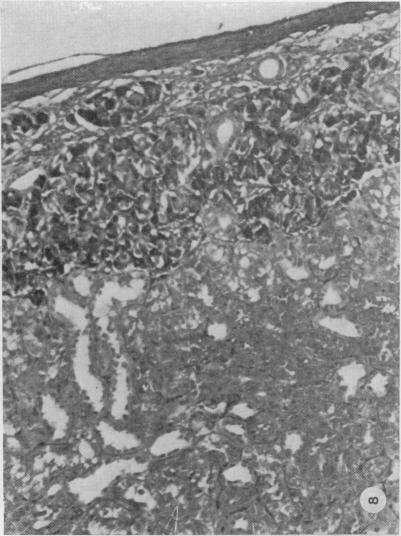

The development of improved methods of islet isolation from the pancreas is hampered by difficulty in identification of islets. A method described by Bensley in 1911 uses neutral red to stain the islets selectively. In the present study the method has been simplified and selective staining of islets in the rat, dog and pig demonstrated by use of light and electron microscopy. Staining of islets with neutral red does not appear to affect their viability as judged by insulin secretion and transplantation in rats.

胰岛从胰腺中分离出来的改良方法的发展受到胰岛识别困难的阻碍。1911年本斯利描述的一种方法使用中性红对胰岛进行选择性染色。在本研究中,该方法已被简化,并通过光学显微镜和电子显微镜证明了在大鼠、狗和猪中胰岛的选择性染色。根据大鼠的胰岛素分泌和移植情况判断,用中性红对胰岛进行染色似乎不会影响其活力。